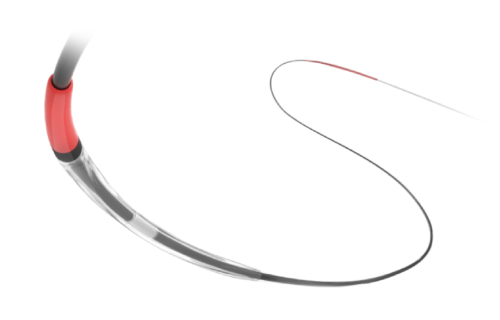

Na área de Cardiologia Intervencionista, fornecemos dispositivos de ponta, como stents, cateteres e balões, que são essenciais para a realização de angioplastias e outros procedimentos cardíacos minimamente invasivos. Nossos produtos são projetados para oferecer máxima eficiência e segurança, contribuindo para a rápida recuperação dos pacientes e a redução de complicações pós-operatórias.

Em Cirurgia Vascular, Endovascular e Radiologia Intervencionista oferecemos uma ampla gama de soluções, incluindo enxertos endovasculares, cateteres de trombectomia e dispositivos de embolização. Esses produtos são vitais para o tratamento de doenças vasculares complexas, como aneurismas e tromboses, proporcionando aos profissionais de saúde as ferramentas necessárias para intervenções precisas e eficazes.